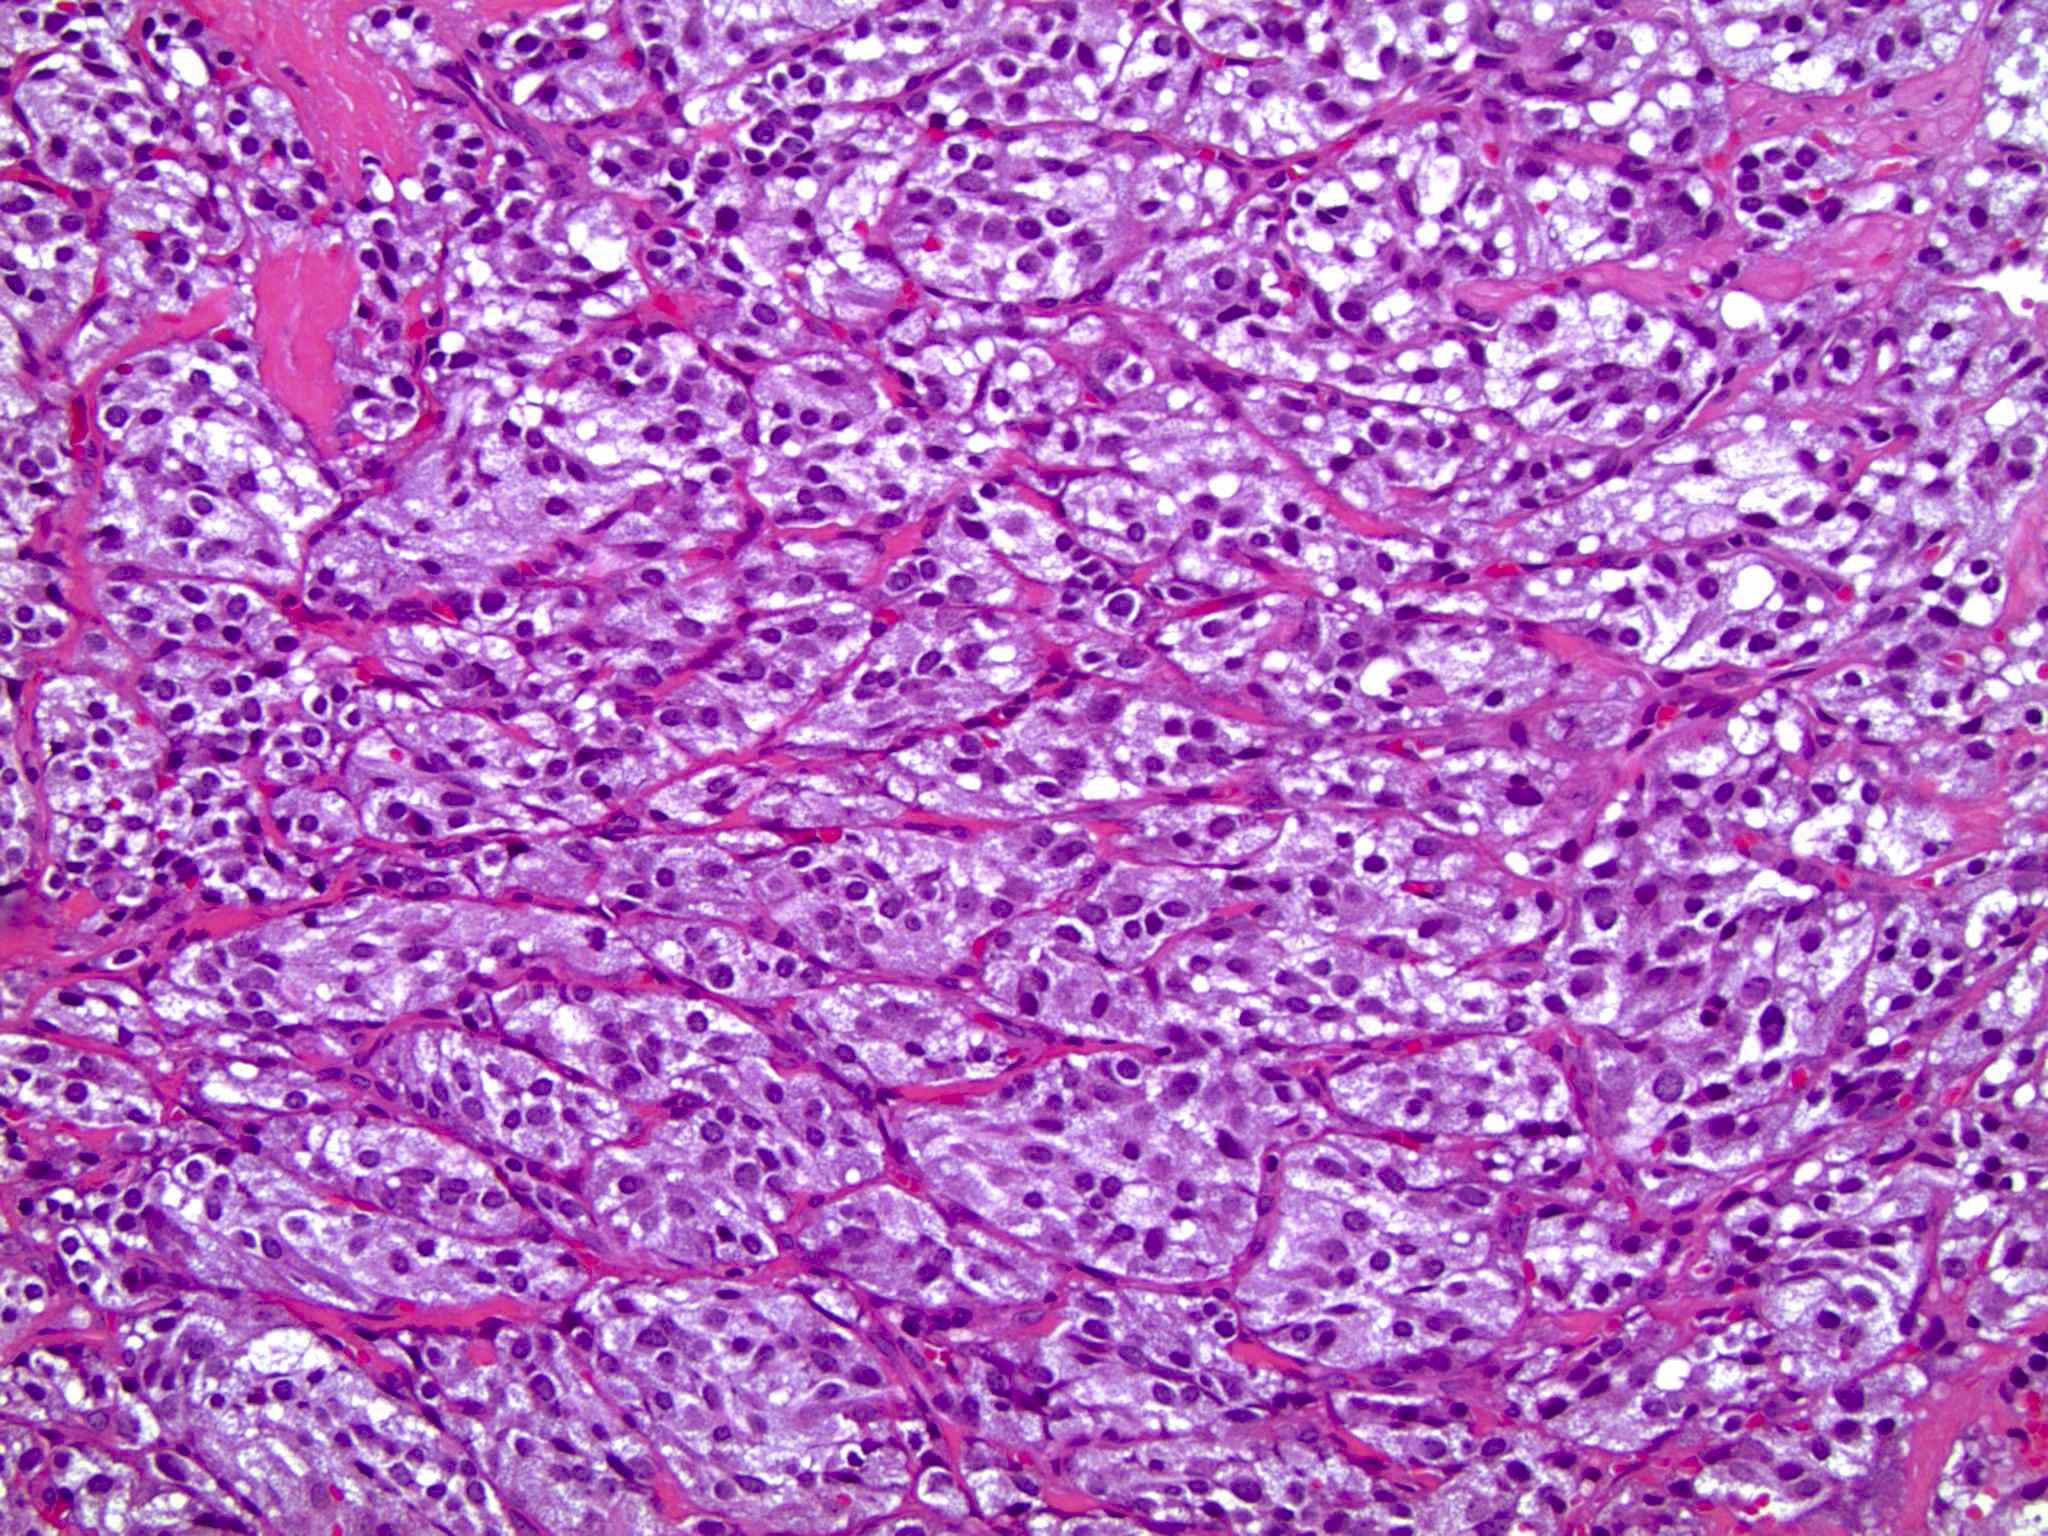

Microscopic (histologic) description

- Typical morphology: epithelioid cells with abundant, eosinophilic / amphophilic, granular cytoplasm and round / ovoid, vesicular / salt and pepper nuclei, arranged in a nested / zellballen pattern and separated by fibrovascular septae with sustentacular cells (Am J Surg Pathol 2004;28:94, World J Clin Cases 2014;2:591, Endocr Pathol 2022;33:90)

- May have focal pleomorphism, nuclear hyperchromasia, low mitotic activity or clear cytoplasm

Microscopic (histologic) images

Contributed by Theodorus H. van der Kwast, M.D., Ph.D., Michelle R. Downes, M.D., Debra L. Zynger, M.D. and David Cohen, M.B.B.Ch., M.D.

- Microscopic description: This specimen shows an unencapsulated, monomorphous population of round tumor cells in a nested / zellballen pattern with delicate vascular septa and intervening extravasated red blood cells. It predominantly involves the lamina propria of the bladder but in 1 tissue piece clearly involves muscularis propria. The tumor cells have abundant amphophilic cytoplasm and vesicular chromatin with occasional small nucleoli. There is no necrosis, diffuse growth pattern or vascular space invasion identified. The mitotic count is (maximally) 1/10 high power fields. Immunohistochemistry shows the tumor cells to be positive for GATA3 with strong and diffuse expression of synaptophysin and chromogranin, as well as retention of SDHB staining. The tumor cells are negative for AE1 / AE3, HMWK and p63. The Ki67 proliferation index is < 1%. S100 shows faint nuclear and cytoplasmic staining with occasional sustentacular cells identified.

- Microscopic description: Sections show unremarkable surface urothelium with a lesion in the deep lamina propria comprised of large eosinophilic cells with hyperchromatic, focally enlarged nuclei with occasional intranuclear inclusions. A fine vascular plexus is identified in some areas. Necrosis and hemorrhage are not identified. Mitotic rate = 1/10 high power fields (field of view [FOV] = 0.55 mm). The lesion extends to the cauterized base of the specimen. Immunostains confirm the lesion expresses synaptophysin, chromogranin and GATA3. SDHB is retained. AE1 / AE3, CD45, p63 and NKX3.1 are negative.